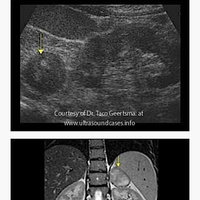

This is a must have pocket reference guide for sonographers, ultrasound students and physicians looking to learn ultrasound. In this ultrasound reference guide you will find normal/abnormal values and descriptions of more than 120 types of diseases and conditions.

o More than 120 diseases and conditions with clinical facts sonographic findings and images

o More than 200 images